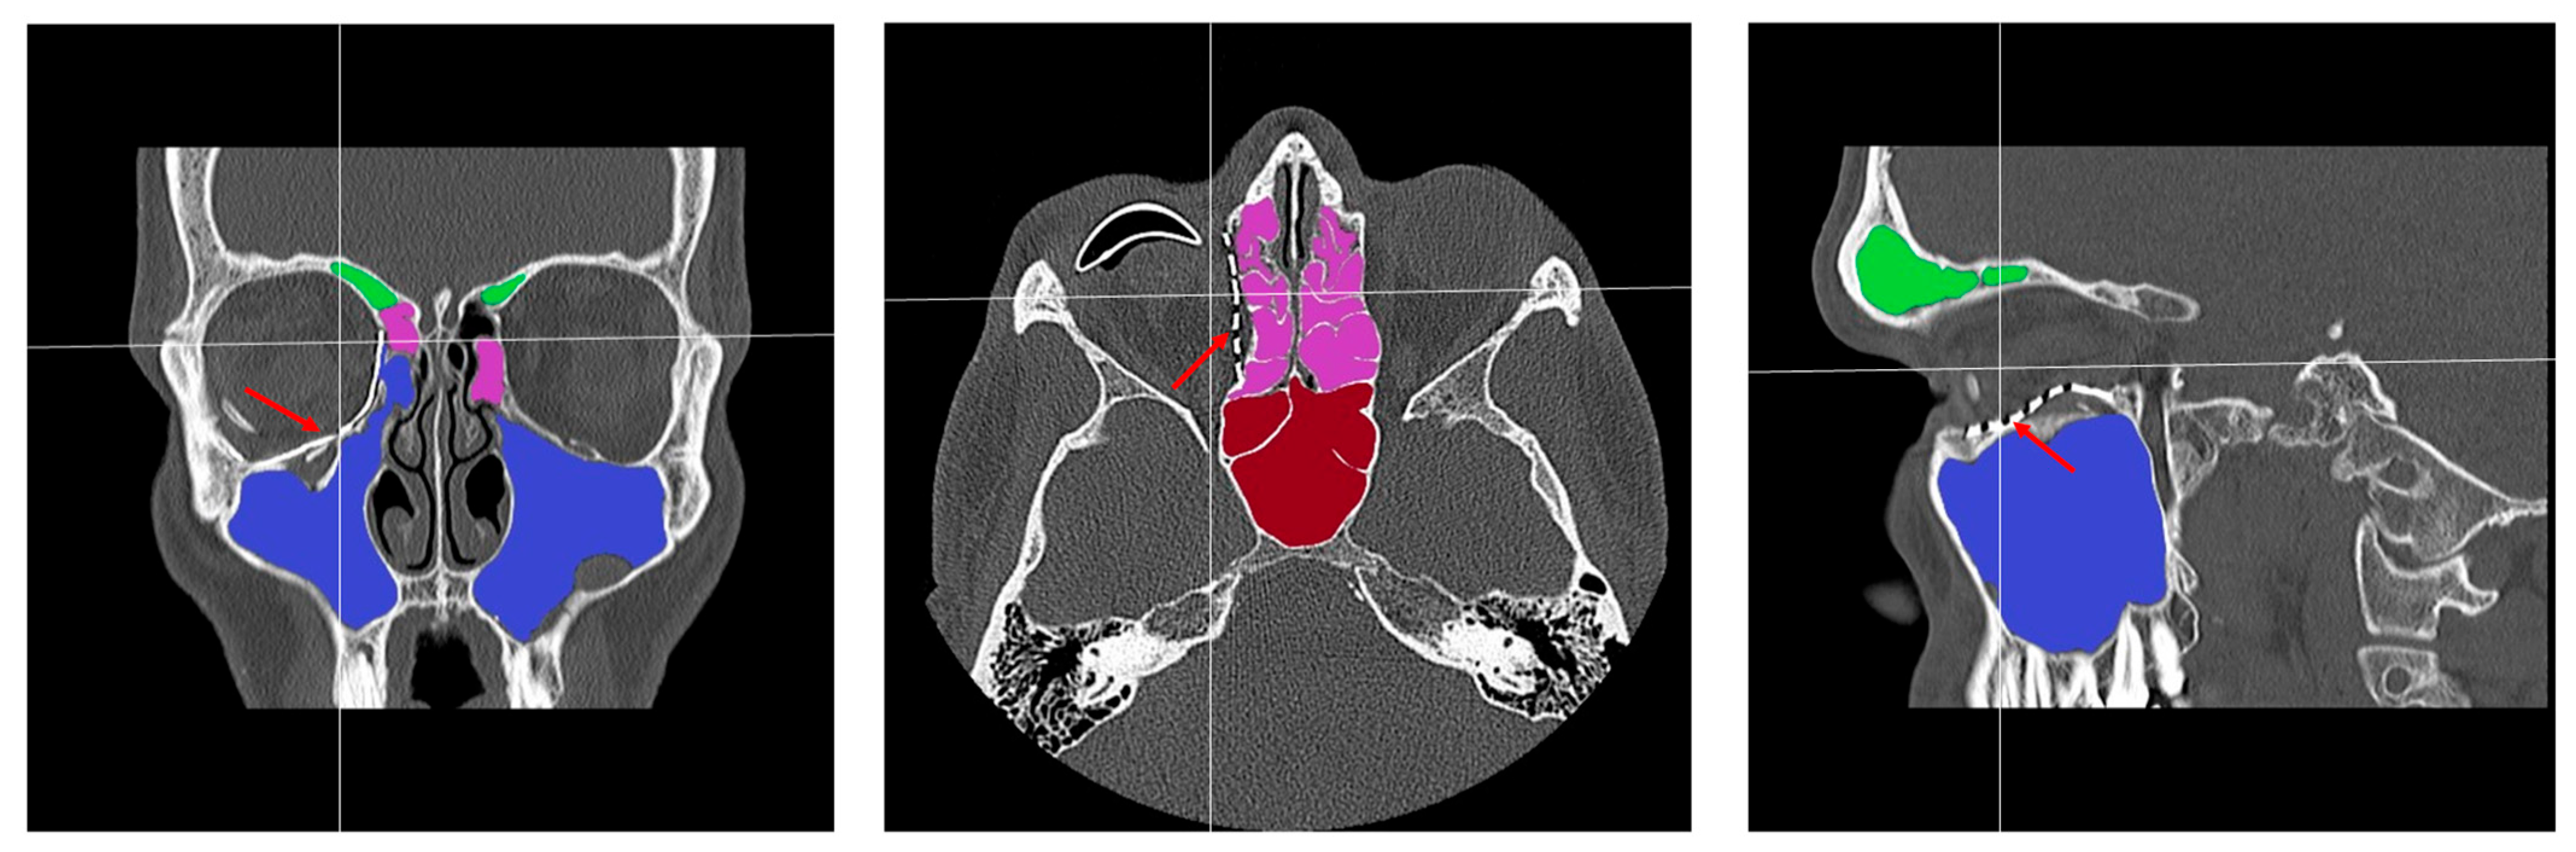

- Patent ostium of the maxillary sinus (coronal plane)

- Non-inflammatory PNSs (three planes)

- Exposure of the osteosynthesis screws (axial and sagittal planes)

- Exposure of the PSI to the maxillary sinus (coronal and sagittal planes)

- Remodeling of the fractured orbital walls and bone apposition at the PSI indicating osseointegration (three planes)

- Patent outflow tract of the maxillary sinus (n = 14) and physiologically ventilated PNSs (maxillary sinus, ethmoid cells, n = 13)

- Exposure of the fixation screws (infraorbital recess of the maxillary sinus) and limited exposure of the PSI (transition zone, ethmoid cells) without signs of mucosal swelling in these regions (n = 6 each)

- (Basal) mucosal swelling in the maxillary sinus indicative of chronic maxillary sinusitis, irrespective of the complexity of the primary injury (n = 4)